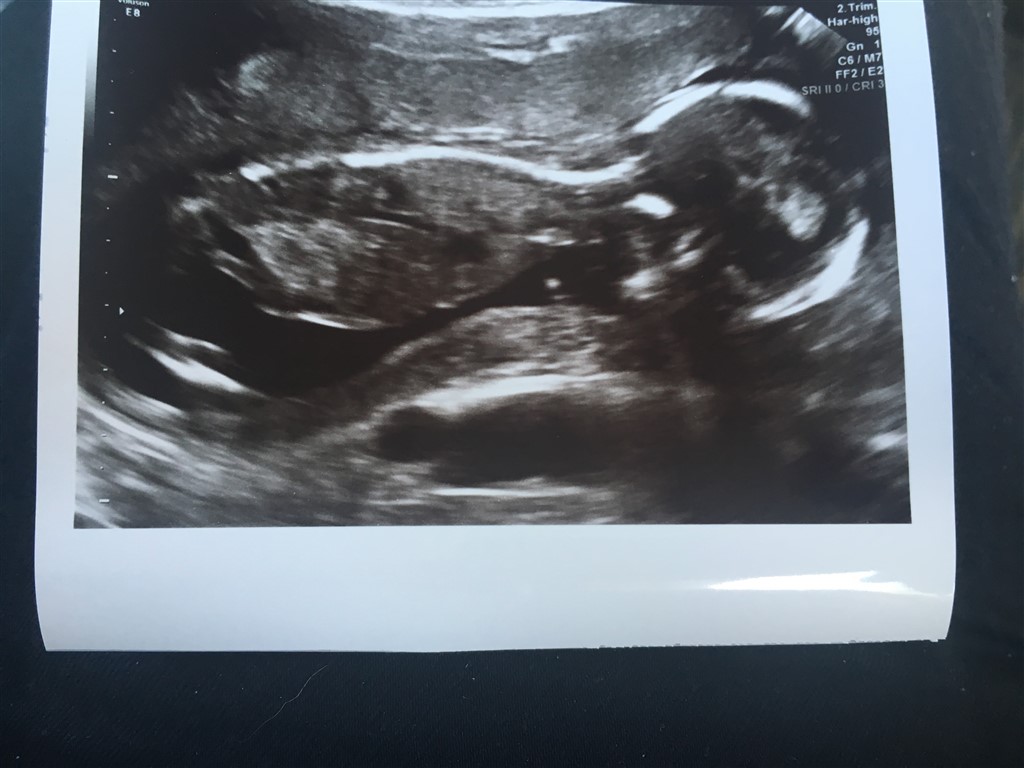

Vil starte med at sige at alt er som det skal være med babyen..

Næstved kunne ikke se kønnet, men babyen er præcis som den skal være. Flot vægt og flot længde. Hjerte, hjerne, lårben alt er lige præcis efter skalaen. Den danser rundt derinde. I forhold til Isaac er der meget meget mere liv denne gang.

Billederne blev knap så gode, for hun er altså en putterøv

Vedhæftede fotos (klik for at se i fuld størrelse)